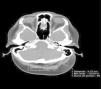

The patient was a 49-year-old Spanish woman with a history of mild to moderate psoriasis involving both the scalp and the nails since the age of 20 years. She had had surgery for breast cancer (T3 N1 M0) 3 years before this consultation and had been receiving treatment with tamoxifen for about 6 months. She came to our clinic because of severe pain and thickening of the scalp, which had started some 3 months earlier, and more recent hair loss in the occipital region. Three weeks earlier, the patient had visited the emergency department of our hospital complaining of severe scalp pain. A computed tomography scan revealed asymmetry in soft tissue volumes, with significant thickening of the subcutaneous layer (3.12cm) in the vertex and left occipital area (Fig. 1).